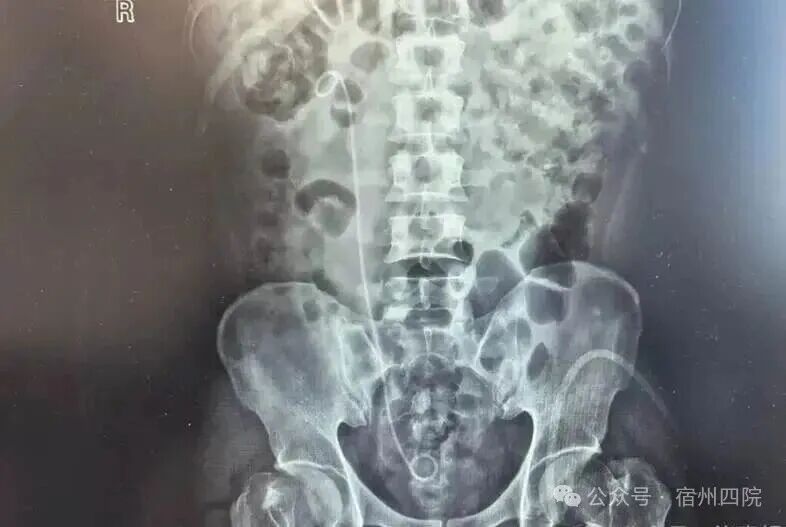

近日,我院泌尿外科为一位右侧尿管结石的患者实施了右侧经尿道输尿管软镜钬激光碎石术,术后次日患者复查无残石,顺利出院。

患者徐某,因结石症状未完全缓解,辗转至我院复查,门诊彩超提示右输尿管上段结石伴肾积水。面对这一情况,泌尿外科团队迅速评估,完善术前检查,排除手术禁忌症后,为患者实施了右侧经尿道输尿管软镜钬激光碎石术。术后次日复查无残石,患者顺利出院,对医院的诊疗技术、服务态度及设备先进性给予了高度评价。